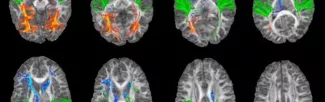

Dyslexia is defined by difficulty learning to read despite average intelligence and motivation. Although what causes dyslexia is unkown, it has been reported to involve other perceptual and cognitive disruptions unrelated to reading skills. This suggests that better understanding of the whole-brain functional connectivity patterns, going beyond the brain's reading networks, is needed. In this talk, Im will present recent resting-state functional magnetic resonance imaging (fMRI) work as an approach to characterizing potential alteration in global wiring patterns of the whole brain in children with dyslexia.